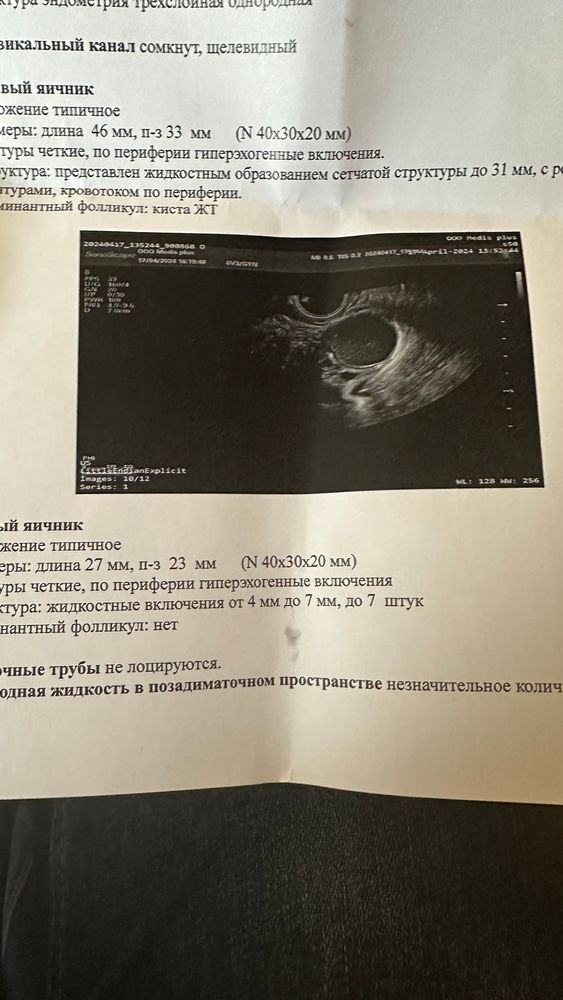

Киста жт или эндометриодная ?

ФолликулометрияХолила на узи после овуляции.Врач сказала понять не может либо киста жт или эндомитриодная…такая надежда была на этот цикл 😟2 дня назад доминантный фолликул был 23мм.У кого было такое что узист не мог понять какая киста и чем закончилось ?